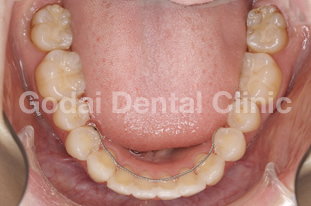

患者様は20代男性、虫歯の治療をしたいことと、歯並びを改善したいという主訴で来院されました。歯医者は10年以上ぶりですが、虫歯も歯並びもしっかり治したいという希望を持っていました。久しぶりの歯医者ということもあり、まずは歯磨きの仕方から改善していきました。歯垢をブラッシングで除去できるようになったところで、虫歯の治療を開始しました。歯並びが悪いこともあり、多くの歯に虫歯が見つかりました。患者様の年齢と歯質の保存を優先し虫歯の治療はコンポジットレジン修復を行いました。また下の親知らずが横向きに生えていたため、左右の親知らずの抜歯を矯正前に行いました。

歯ブラシの改善と虫歯の治療、親知らずの抜歯が終わったところで、矯正治療へ移行しました。患者様は健康な歯を抜きたくないという希望を持っていたので非抜歯の治療計画を立てました。まずは上下顎ともに拡大装置を用い歯列の拡大を行いました。その後、アライナーを使ったインビザライン矯正治療へ移行し、歯並びの修正と咬み合せの確立を行いました。拡大装置を使っている際は、口内炎や話しずらさなどがあったそうですが、インビザライン治療に移行してからは痛みも話しずらさもなくなり快適に過ごせたそうです。もともと多くの虫歯があったため矯正中の虫歯が心配でしたが、インビザライン矯正治療を選択したことで、新しい虫歯を作らずに治療を終えることができました。

歯並びを改善したい場合でも、歯磨きの確立、虫歯の治療、親知らずの抜歯など矯正前に治療が必要な場合もあります。ただ矯正前の治療をしっかりと行うことで、矯正治療の結果がより良いものになりますし、治療もスムーズに進みます。最終的に患者様にとって最善の治療になるよう心がけて治療を行っています。口の中が心配な方は、いつでもご相談ください。

治療前1

治療後1

治療前2

治療後2

治療前3

治療後3

治療前3

治療後3

治療前3

治療後3